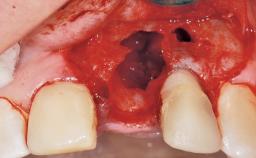

A 42-year-old female patient was referred to our clinic at the School of Dentistry of the University of São Paulo in November 2004, presenting a deficient restoration in the upper left central incisor. The clinical examination revealed no gingival retraction or any signs of gingival inflammation and, therefore, previous periodontal treatment was not considered. The patient presented a high lip line at full smile and a thin tissue biotype. This combination characterized a high-risk situation from an anatomic point of view, which required careful preoperative planning and cautious surgical execution.

Soft Tissue Anatomy Intact Defective

Bone Volume Horizontally and vertically sufficient Horizontally deficient Deficient vertically or deficient vertically AND horizontally

Socket Integrity Sufficient, with intact bone walls

Bone Volume Sufficient, with intact walls

Soft Tissue Contour and Volume Ideal